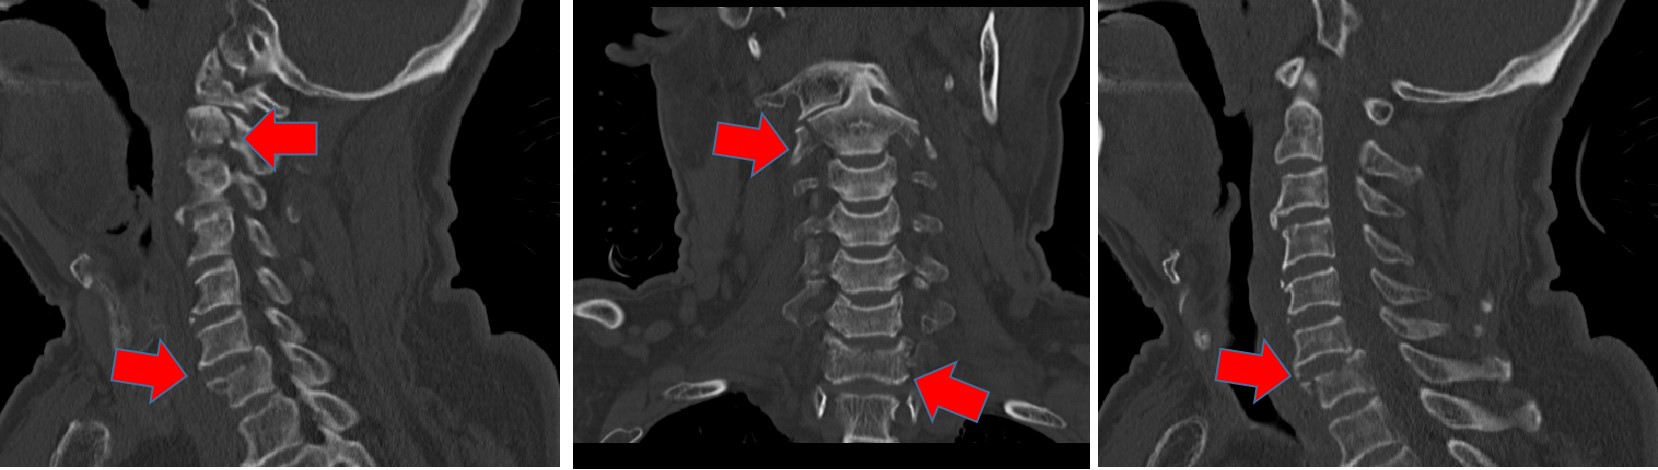

CT可见多处颈胸椎骨折

“我太幸运了,赶上回家过年真好啊!”腊月二十八出院的李爷爷(化名)感慨道。就在半个多月前,70岁的他过马路时却被汽车当场撞飞。经当地医院检查,从颈椎第一节直到胸椎第二节全部骨折,其中人体脊柱最关键的颈椎第二节——枢椎,粉碎性骨折。大面积骨折压迫脊髓,导致老人的四肢出现不完全性瘫痪。

由于老人年事已高,发生骨折的位置又很棘手,加上有明确的脊髓损伤,一家人辗转多个医院都没能被收治,直至来到清华长庚神经外科。孙振兴医师接诊后,和科室医生张培海、荆林凯讨论,一致认为如果不能将患者断掉的脊柱重新扶直、固定的话,他根本无法翻身活动,随时有二次脊髓损伤加重的风险,届时就是高位截瘫。而这个年纪的高位截瘫对老人意味着什么?神外团队决定挑战一把!